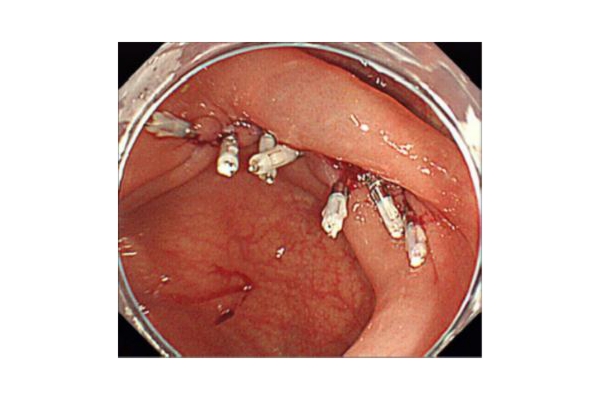

《胃ESDの実際》

食道表在癌、早期胃癌の治療法として当科では積極的にESDを行っています。ESDとは内視鏡的に使用可能な高周波メスを使って、粘膜下層のレベルで病変を剥がし取る手技です。早期の小さな癌に対しては今までも内視鏡治療が行われてきましたが、ESDにより従来の内視鏡治療法(EMR)では切除困難であった大きな病変や、瘢痕を認める病変を一括切除できるようになりました。体を切開することなく組織も温存できるため、患者の身体的負担が少ない低侵襲医療のひとつです。

食道ESDは年間約15例、胃ESDは年間約40例ほど行っております。